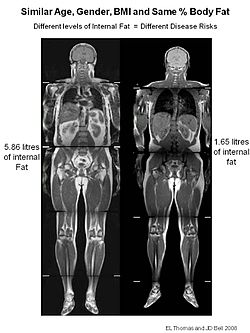

胸部と腹部の冠状面および矢状面のctスキャン 写真背景 無料ダウンロードのための画像 - Pngtree。

胸部と腹部の冠状面および矢状面のctスキャン 写真背景 無料ダウンロードのための画像 - Pngtree。

胸部と腹部の冠状面および矢状面のctスキャン 写真背景 無料ダウンロードのための画像 - Pngtree。

ヘリカルCTは横断面だけではなく矢状面や冠状面も作ることができます!ふかつ泌尿器科・皮ふ科クリニック。